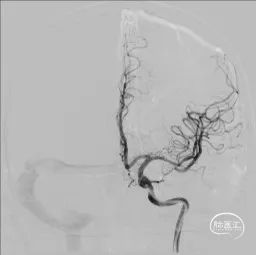

在大脑中动脉M1末端及上干起始段置入赛诺神畅 颅内药物支架NOVA DES®2.25*10mm,球囊扩张成形,支架成形好,狭窄处扩张好,下干未闭塞。

支架释放

全脑及病变处不同体位造影:狭窄处成形好,未残余明显狭窄,左大脑中动脉主干及各分支显影好。

术中将Navien导管送至颈内动脉岩骨段,增加支撑力,将两条微导丝分别送入左大脑中动脉上下干,先沿上干微导丝送入球囊扩张,效果差, 再沿下干微导丝送入球囊扩张,效果仍差,大脑中动脉M1末端狭窄有改善,但狭窄仍较重,遂用赛诺神畅 颅内药物支架NOVA DES®2.25*10mm置入左大脑中动脉M1末端及上干内,球囊扩张成形,支架成形好,血管成形满意,确定下干无闭塞后,撤出下干微导丝。